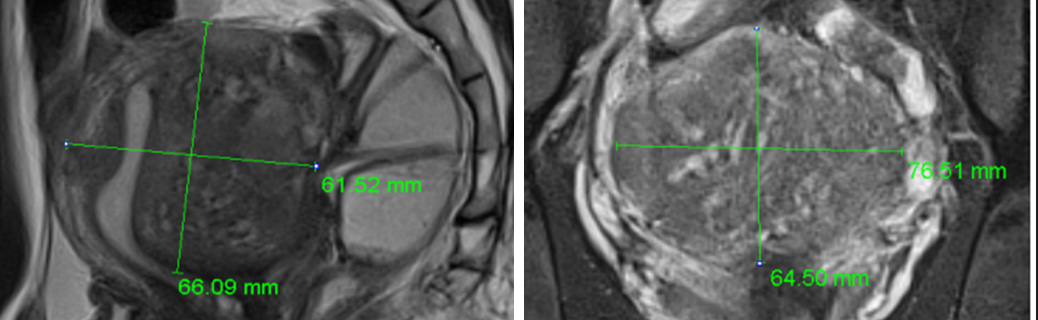

심한 생리통과 항문통증으로 자궁선근증이 진단되어 자궁선근증 하이푸 치료를 위해 입원하셨습니다.

하이푸 시술전 MRI사진상 자궁은 6.5크기로 커져서 자궁후벽을 중심으로 자궁선근증성 변화가 관찰됩니다.

아래의 MRI 사진은 자궁선근증 하이푸 시술 전후의 사진을 비교한 사진입니다. 자궁선근증 하이푸 치료후 90%이상 치료되어 치료부위가 회색과 검은색으로

나타나며, 차후에 좋은 경과를 기대하며 가장자리의 잔여병변은 호르몬 치료하면서 경과관찰 하시도록 하였습니다.